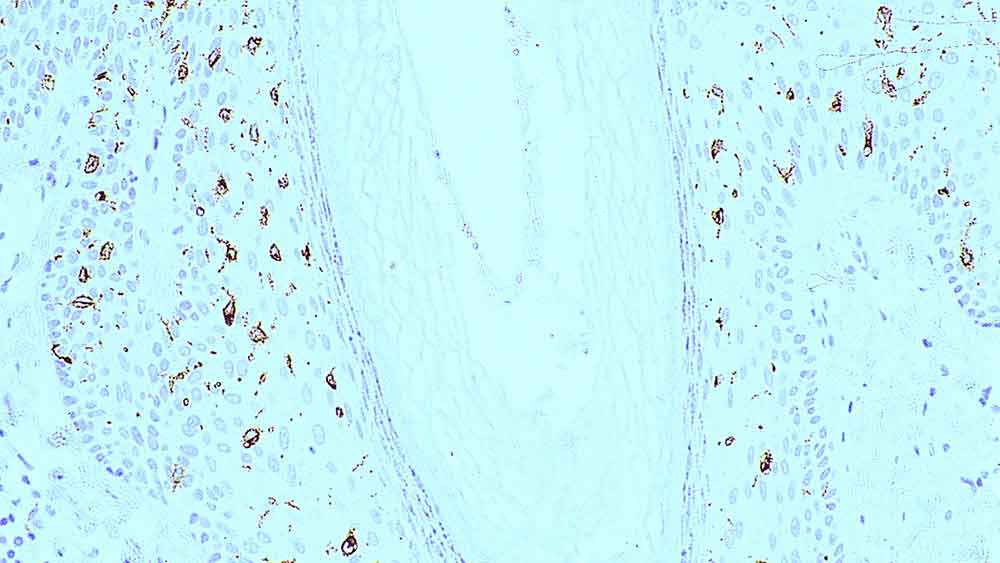

Human skin: immunohistochemical staining for langerin. Langerin: clone 12D6

Langerin is a type II transmembrane C-type lectin which has mannose-binding specificity. It is a 40 kD protein restricted to Langerhans cells that is involved in the internalization of cell surface material in these immature dendritic cells. Dendritic cells are antigen-presenting cells that are required for initiation of a specific T-cell-driven immune response. These cells are found in non-lymphoid tissue as immature cells whose primary function is to capture antigens through specialized surface membrane endocytic structures or through macropinocytosis. The dendritic cells migrate to secondary lymphoid tissue and mature into efficient antigen presenting cells. A part of the maturation process includes the loss of adhesion receptors such as E-cadherin and the disappearance of Birbeck granules. Although Langerin is reported to be located on the cell surface, it can be rapidly internalized following ligand capture into Birbeck granules. In fact, Langerin is a potent inducer of membrane superimposition and zippering leading to Birbeck granule formation. In reports it has been suggested that the induction of Birbeck granules is a consequence of the antigen-capture function of Langerin allowing passage into these organelles and providing access to a non-classical antigen processing pathway.